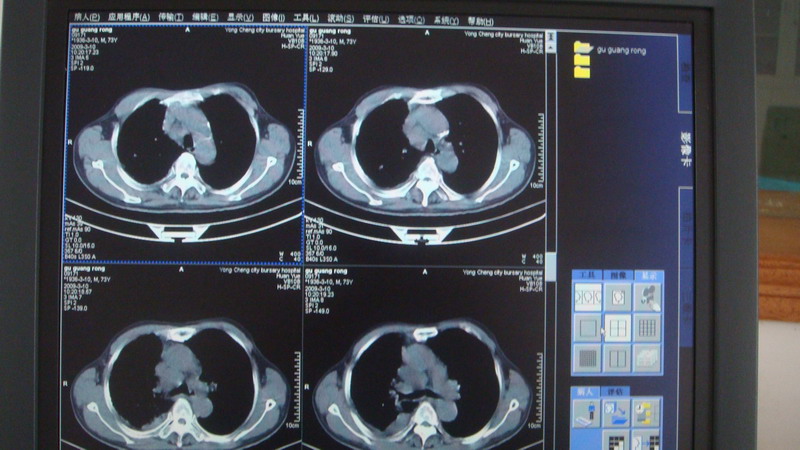

以下是引用光影相伴在2009-3-11 17:27:00的发言:[br]支持 右肺下叶周围型肺癌伴右肺门纵隔淋巴结转移;右上肺继发型肺结核(硬结\\纤维灶);右侧少量胸胸腔积液。另:不排除右侧胸膜转移可能。

以下是引用随光逐影在2009-3-11 16:57:00的发言:[br]支持 右肺下叶周围型肺癌伴右肺门纵隔淋巴结转移;右上肺继发型肺结核(硬结\\纤维灶);右侧少量胸胸腔积液。另:不排除右侧胸膜转移可能。

以下是引用草之原在2009-3-11 19:03:00的发言:[br]支持 右肺下叶周围型肺癌伴右肺门纵隔淋巴结转移;右上肺继发型肺结核(硬结\\纤维灶);右侧少量胸胸腔积液。另:不排除右侧胸膜转移可能。